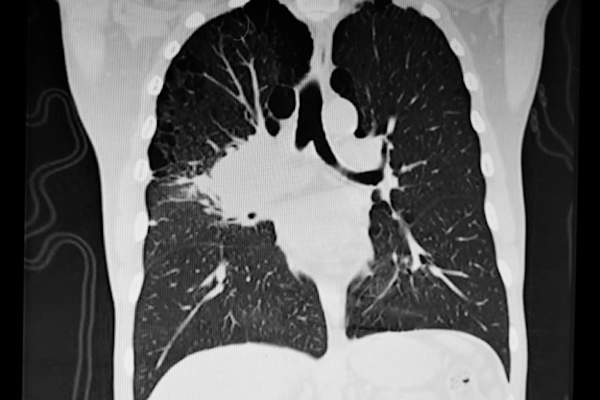

肺转移的迹象

当它确实引起症状时,这些迹象很难与普通感冒区分开来。如果问题持续了一两个星期以上,那就检查一下,breastcancer.org建议。

症状可能包括:

- 肺或胸部疼痛或不适

- 呼吸困难;喘息

- 持续的咳嗽

- 咳出血或粘液的

- 腹部或胸部的x光片或超声波

- 支气管镜检查